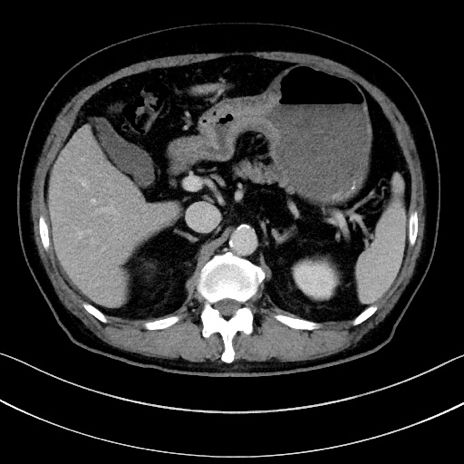

冠状断像

【症例】70歳代男性

【主訴】腹痛

【現病歴】今朝から腹痛あり。全体的に痛い。特に左上の方。排ガスが今日はない。冷や汗が出る。

【既往歴】直腸癌術後

【身体所見】左側腹部〜上腹部に圧痛あり。腹膜刺激症状明らかなではない。軽度反跳痛。左下腹部に術後瘢痕あり。

【データ】WBC 7700、CRP 0.02